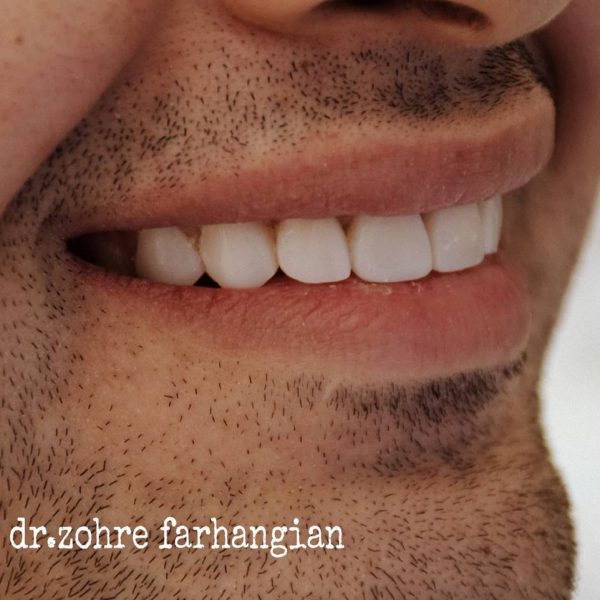

نمونه کار شماره ۲۰ کامپوزیت ونیر

۷ واحد ونیر کامپوزیت با رنگ طبیعی برای فک بالا

مراحل درمان به شرح زیر:

۱.ریموو کردن کامپوزیت ونیر چهاردندان قدامی (به علت ناراضی بودنشون از آناتومی دندونها)

۲.انجام ۷واحد ونیر کامپوزیت با رنگ طبیعی

۳.و یک واحد رزین بانددبریج برای دندان پره مولر اول سمت چپ بصورت موقت (که در آینده ایمپلنت خواهد شد.)

طراحی لبخند زیبا 😍